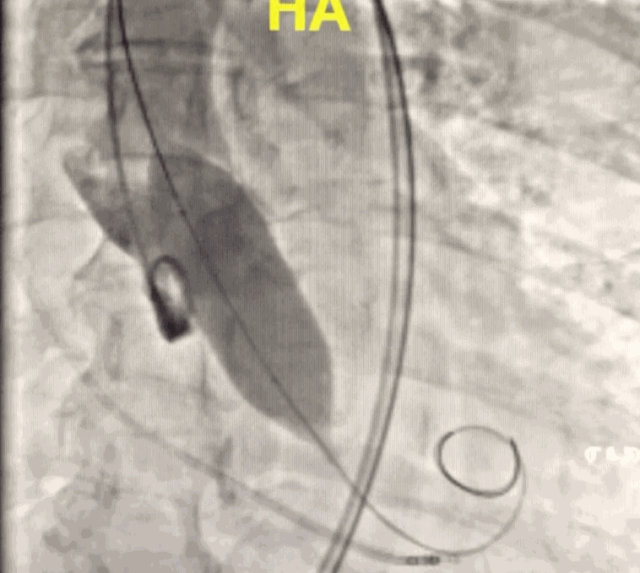

TAVI,指经导管的主动脉瓣置换,不开胸或胸部小切口的辅助下,逆行或顺行将处理好的瓣膜输送至主动脉根部,在不处理原瓣膜的情况下进行主动脉瓣置换。手术操作时间短,是当今国际上最先进的外科技术之一,对于高危的患者,是更为合适的治疗策略。

TAVI术中利用放射线置入瓣膜

2019年12月23日,北京大学国际医院收治一位70多岁高龄、符合TAVI手术指征的患者。经心外科、心内科、放射科、麻醉科、超声科、重症医学科等多学科会诊,在中国医学科学院阜外医院结构心脏中心王巍主任、王旭主任医师的指导下,北京大学国际医院第一台TAVI手术如期进行。手术进行2个小时,术后复查超声结果十分满意,患者术后4天恢复良好,复查结果满意,已达到出院指征。